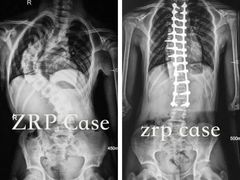

• 南方医科大学第三附属医院

• -南方医科大学第三附属医院